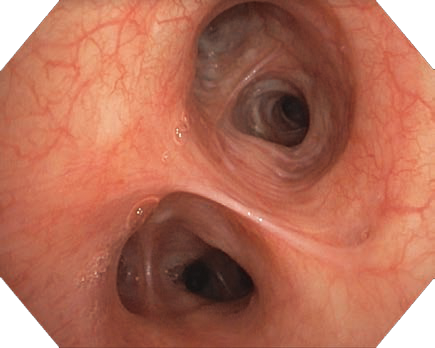

-              ハイビジョンハイビジョン対応のCCDを搭載。高精細なハイビジョン画像を提供します。ビデオシステムセンターもノイズの大幅な低減により、画像の鮮明さが飛躍的に向上。気管支表面のより高精度な観察・診断をサポートします。

電子拡大機能

内視鏡画像をボタンひとつで電子的に拡大します。高画質を維持したまま、1.2/1.5倍の拡大観察が可能です。